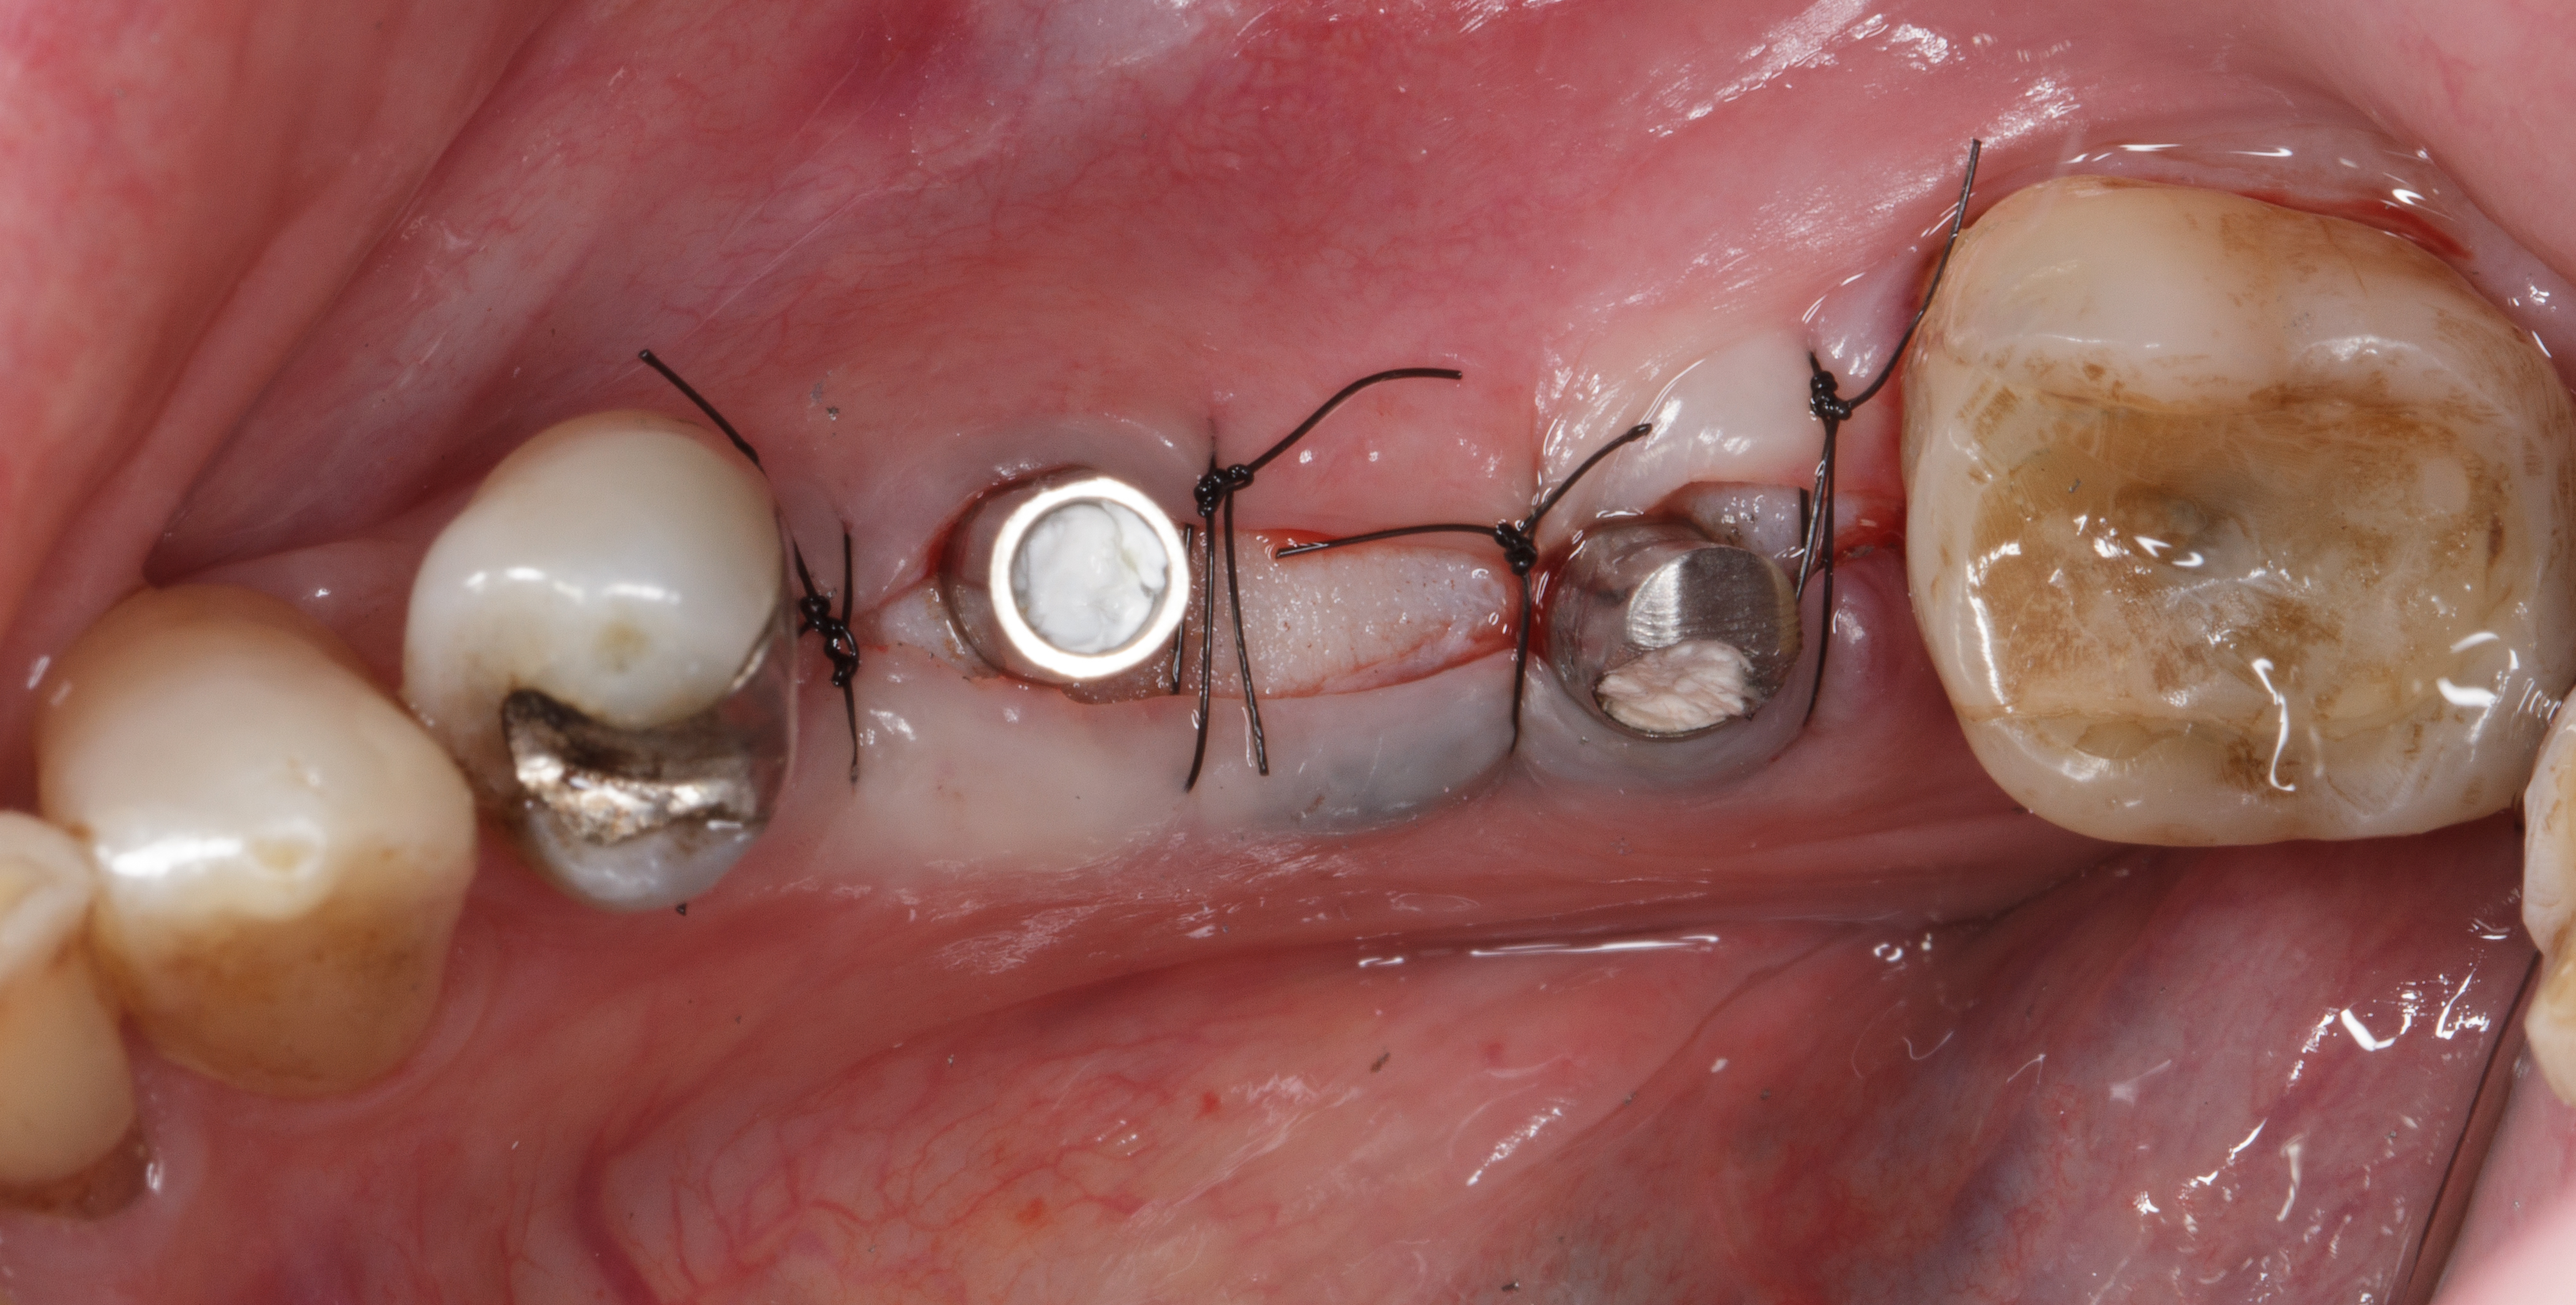

Prima di procedere con la sutura del lembo viene posizionata una membrana riassorbibile in collagene NeoGen® Flex per consentire la stabilizzazione dell’osso crestale e una miglior maturazione del particolato in fase di integrazione ossea. Si esegue una sutura a punti staccati (Figure 15-17).

Dopo sei mesi dall’intervento di preservazione alveolare si inserisce un impianto differito in posizione 4.5.